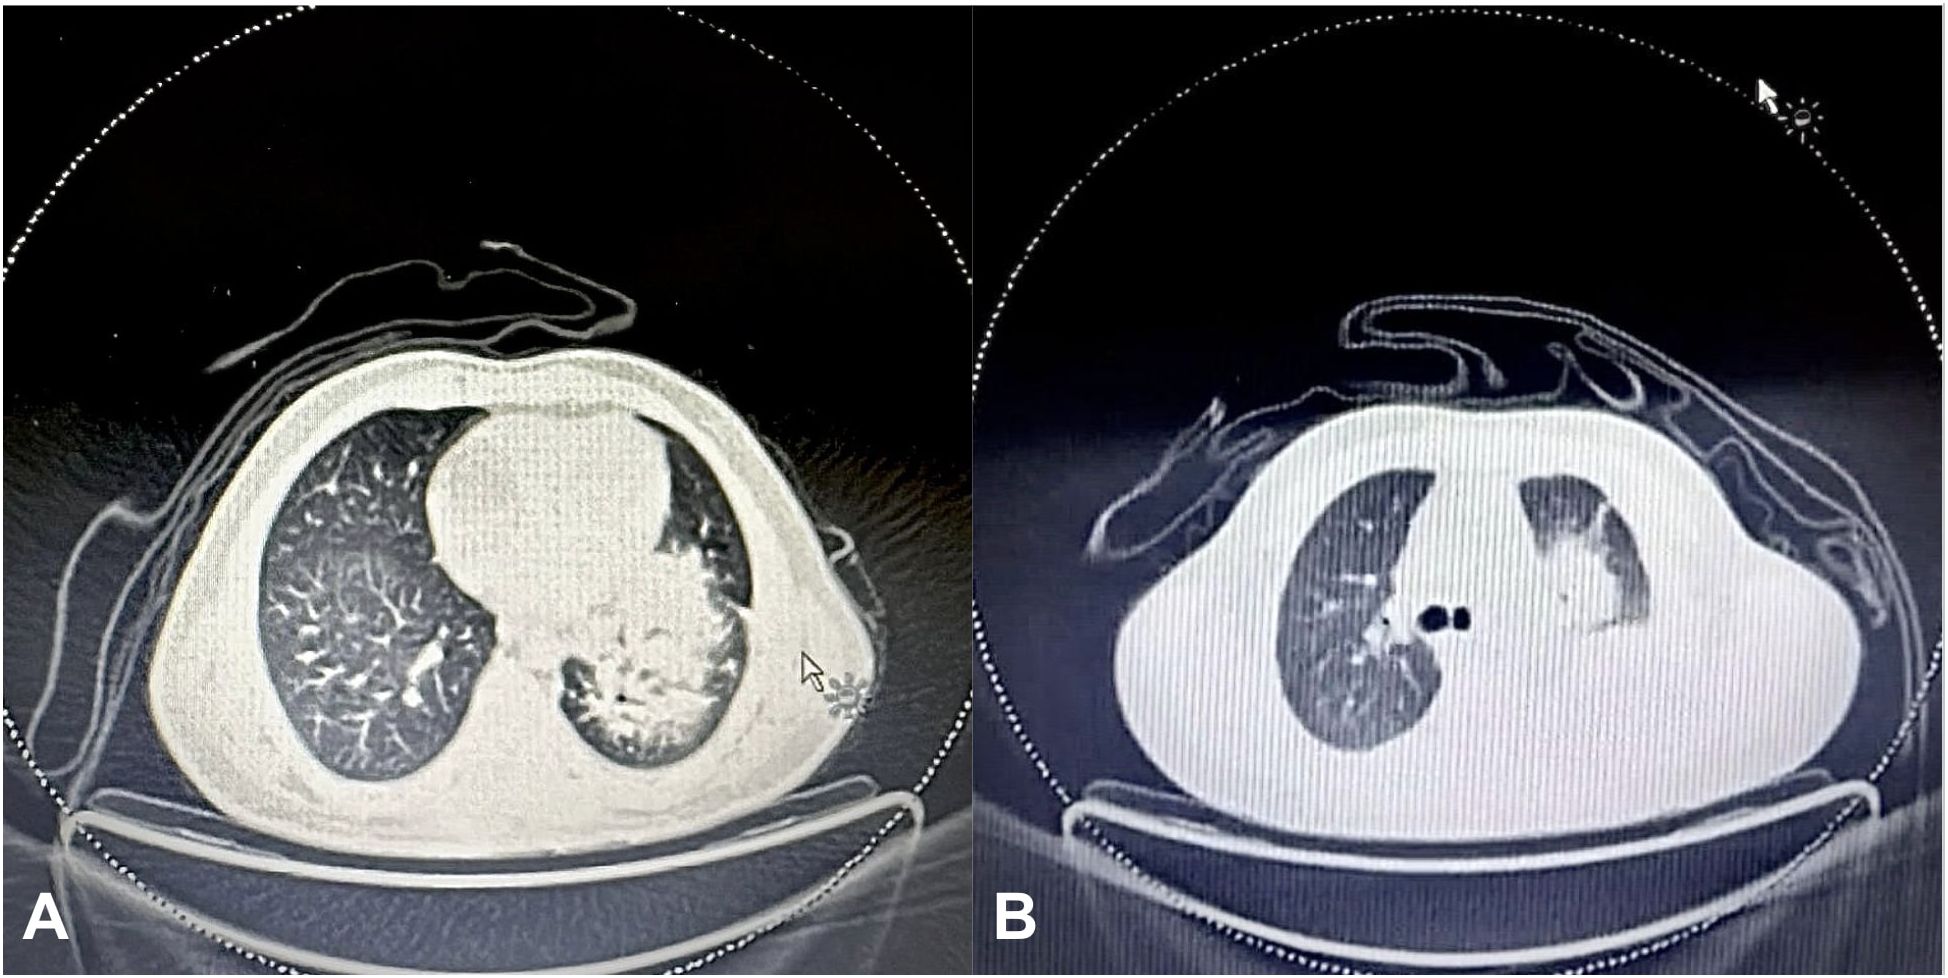

Two CT scans of a thoracic section are shown side by side. Image A displays a scan with visible lung structures and surrounding tissues, while Image B shows a similar scan with slight differences in tissue density and structure visibility. Both images highlight variations in lung appearance.

Figure 3. (A) Initial FDG PET scan of the chest showing an 11x11x10 cm soft tissue mass in the left lung perihilar region, encasing the left lobar bronchus and extending from the medial pleural surface to the lung periphery. (B) Final FDG PET scan showing a marked interval increase in the size of the soft tissue mass in the left lung perihilar region (12x12x8 cm), extending into the upper and lower lobes and reaching the pleural and pericardial surfaces.